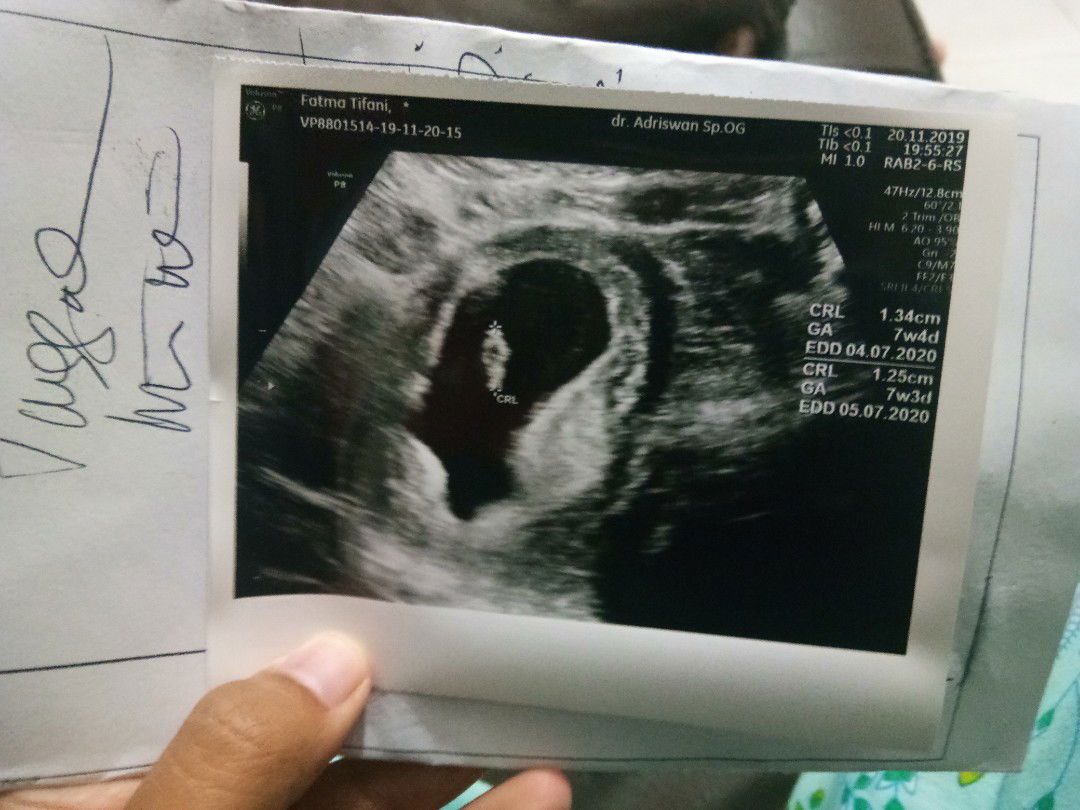

Bun pernahkah selama hamil flek? Awal pertama kedokter ukurang 6 minggu janin belum terlihat Trus diusg 2 minggu lagi janin udah kelihatan dan bagus Lalu diresep kan obat penguat tpi sesudah memakai malalui vagina flek bun Trus 2 hari lagi bali kedokter kata dokternya gpp bun obatnya gak dimasukin ke vagina lagi Tpi diminum 2 kali sehari Tpi kok saya masih tetap flek yg bun Gak sampe di celana dalam Tpi nempeh gitu kuk keputihan Adakah bunda-bunda disini yang mengalamin?